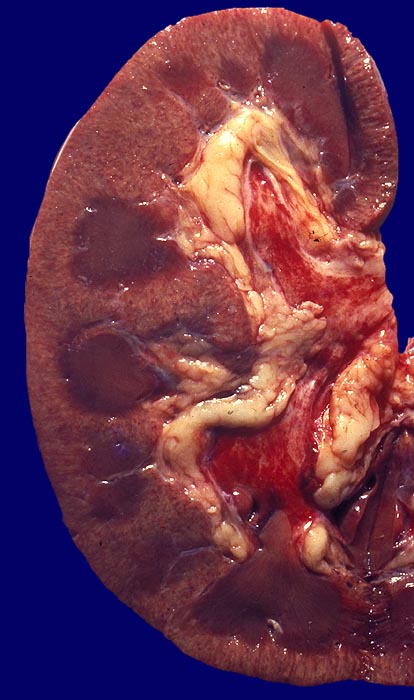

Makroskopie

Befund

Pathologischer Befund

Normalbefund